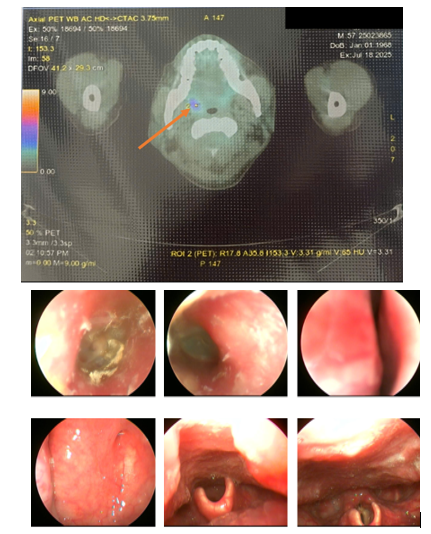

Chụp cắt lớp phát xạ positron PET/CT:

- Hình ảnh vài hạch thượng đòn trái (SUVmax: 2.85), nhiều hạch ổ bụng (SUVmax: 4.89), hạch chậu hai bên (SUVmax: 4.66) tăng chuyển hóa FDG tương ứng với hạch ác tính. Đối chiếu với mô bệnh học, hóa mô miễn dịch.

- Hình ảnh tổn thương khuyết xương ở thân đốt sống L4, xương chậu phải, xương mu phải, tăng chuyển hóa FDG khả năng ác tính (SUVmax: 3.08).

- Hình ảnh tăng chuyển hóa FDG ở amidam bên phải (SUVmax: 3.71) Đối chiếu với nội soi.

- Hình ảnh nốt giảm tỷ trọng ở nhu mô gan hạ phân thùy IV, tăng nhẹ chuyển hóa FDG (SUVmax: 2.76). Cần phối hợp đánh giá thêm.

- Hình ảnh vài nốt mờ dưới màng phổi và sát rãnh liên thùy ở thùy dưới phổi phải và thùy trên phổi trái, không tăng chuyển hóa FDG. Nên lưu ý bệnh lý viêm. (Đối chiếu với CT scanner lồng ngực: phù hợp với hình ảnh)

Hình 1. Hình ảnh PET/CT toàn thân của bệnh nhân.

Hình 2. Hình ảnh tăng chuyển hóa FDG ở amidam bên phải với SUVmax: 3.71 (được ký hiệu bằng mũi tên màu da cam, hình trên). Tuy nhiên, khi đối chiếu với hình ảnh nội soi tai mũi họng lại không có tổn thương nghi ngờ ác tính (Hình dưới).

Hình 3. Hình ảnh nhiều hạch ổ bụng (SUVmax: 4.89) tăng chuyển hóa FDG tương ứng với hạch ác tính (mũi tên đỏ). Đối chiếu với mô bệnh học, hóa mô miễn dịch.

Hình 4. Hình ảnh tổn thương xương chậu phải (mũi tên màu da cam), xương mu phải (mùi tên màu vàng), tăng chuyển hóa FDG khả năng ác tính (SUVmax: 3.08); hạch bẹn 2 bên tăng chuyển hóa FDG, với tổn thương có kích thước lớn và tăng bắt FDG rõ rệt ở hạch bẹn phải (mũi tên vàng), SUVmax: 4,66.

CT ngực, MRI ổ bụng, CT sọ não cũng không phát hiện được tổn thương nguyên phát. Trường hợp này của bệnh nhân là chỉ định tuyệt đối của chụp PET/CT nhằm tìm ra vị trí nghi ngờ có khả năng ung thư cao nhất.

Kết quả PET/CT toàn thân của bệnh nhân tuy không phát hiện được tổn thương nguyên phát, nhưng phát hiện được rất nhiều các tổn thương di căn hạch trong ổ bụng-tiểu khung như nhiều hạch cạnh động mạch chủ, hạch dọc bó mạch chậu 2 bên với kích thước lớn và SUVmax cao, ngoài ra còn có xương đốt sống, cánh chậu, và gan. Với những thông tin có được từ PET/CT, bác sĩ lâm sàng có thể lựa chọn các vị trí khác nhau để sinh thiết lại tổn thương tìm nguồn gốc u (ví dụ: xương, gan). Đồng thời cũng đặt ra cân nhắc về nội soi tai mũi họng lần thứ hai để khẳng định lại tính chất của tổn thương amidan phải phát hiện trên PET/CT nhưng chưa nhìn được trong nội soi tai mũi họng lần đầu tiên.